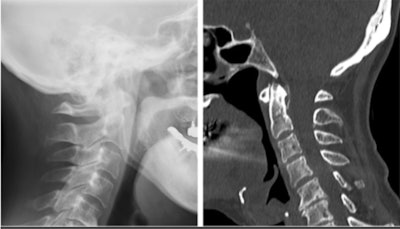

Comparison of a cervical sagittal radiograph and CT scan. Calcification around the odontoid process is not visible on a radiograph. Images courtesy of Mosuda et al. Licensed under CC BY-NC-ND 4.0.

A cervical x-ray showed no abnormalities. However, a cervical computed tomography scan revealed calcification surrounding the odontoid process, which was consistent with crowned dens syndrome, they wrote.